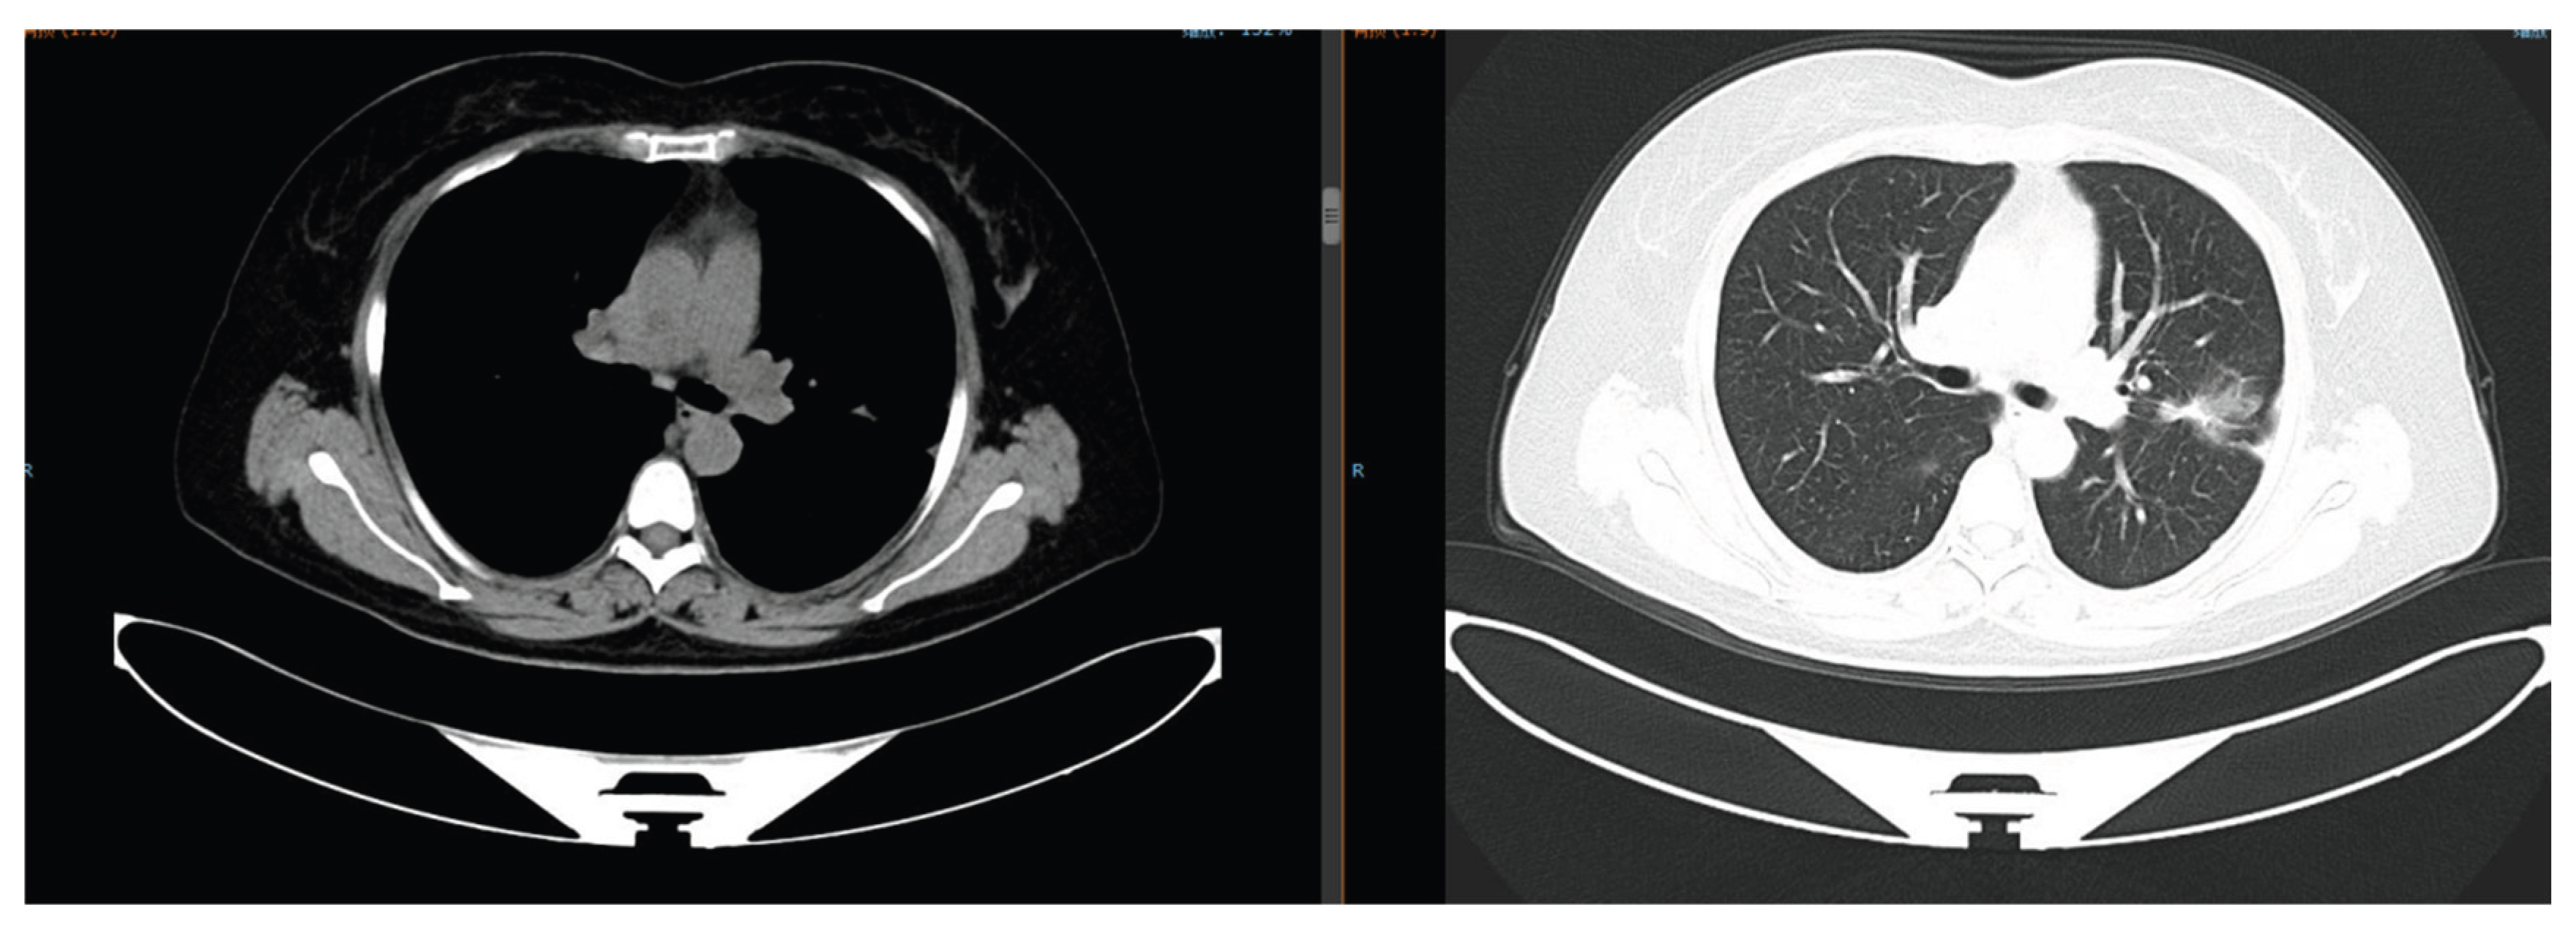

The patient presented with cough and expectoration. Chest computed tomography (CT) revealed multiple bilateral pulmonary nodules (maximum diameter: 3.5 cm) with moderate right pleural effusion (Figure 1). Pathological examination of the pleural effusion confirmed adenocarcinoma (Figure 2), and next-generation sequencing (NGS) detected an EGFR exon 19 deletion mutation. She was diagnosed with advanced lung adenocarcinoma (cT4N2M1 Stage Ⅳ). Treatment included the first-generation TKI gefitinib (250 mg orally once daily) and cisplatin intrapleural perfusion. Two months later, the pleural effusion completely resolved, and the pulmonary nodules reduced by 50%, achieving a partial response (PR) (Figure 3).

Figure 1. Chest CT on September 11, 2019: Multiple bilateral pulmonary nodules (maximum diameter 3.5 cm) with right pleural effusion.